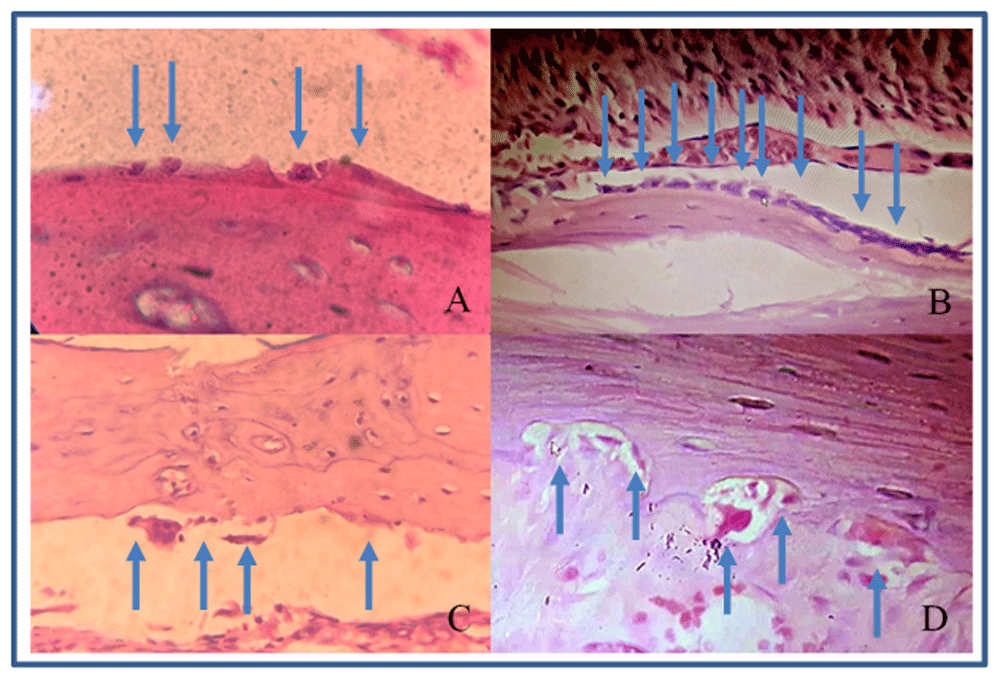

The number of osteoblasts in group 2 were higher compared with group 1 at each time point (Figure 2A and B; Table 2). These differences were statistically significant (p<0.05). Group 2 showed increased osteoblasts starting from day 0 to day 3, while group 1 had decreased osteoblast after day 3.

(A) osteoblasts in group 1 (control); (B) osteoblasts in group 2 (vitamin E treatment); (C) osteoclasts in group 1; (D) osteoclasts in a Howship’s lacuna in group 2.

The number of osteoclasts in group 2 were higher than group 1 except on day 1, but the differences were not significant statistically (Figure 2C and D; Table 3).